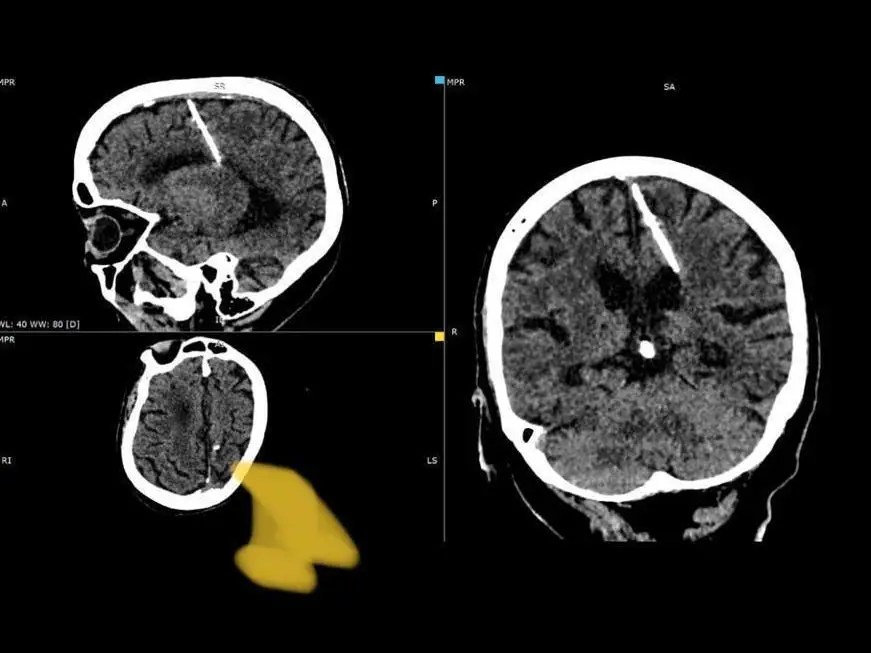

During a startling revelation, doctors in Russia’s far east discovered a 3 cm-long needle embedded in the brain of an 80-year-old woman during a routine CT scan. The medical team believes the needle has been lodged in her brain since birth and suggests a distressing history of infanticide during the Second World War due to times of famine and financial unstableness in Russia. An infanticide is the act of killing an infant, typically within the first year of life.

Food shortages were rampant in the Soviet Union during the war, and impoverished families resorted to such measures. Remarkably, the woman survived, and despite the needle in her brain, she had never complained of headaches and was not deemed to be in immediate danger. Medical experts have opted to monitor her condition, refraining from attempting needle removal due to concerns about potential worsening of her health.